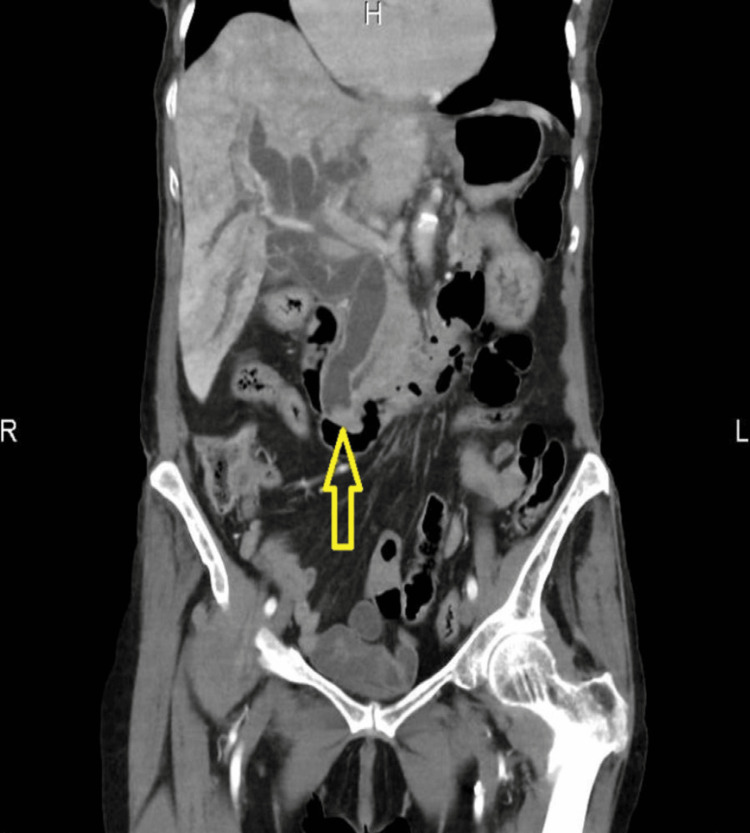

A 93-year-old lady was brought into the emergency department (ED) of the hospital by ambulance following a fall at home. Initially, she had a fall two days ago in the kitchen when she noticed her right leg gave away. Following, she had a similar fall while coming out of bed and called the ambulance leading to her being escorted to the hospital. On arrival, she was found to be hemodynamically stable, but with obvious swelling of the right knee and unable to weight bear. She was reviewed by the orthopaedic team, and imaging suggested a large effusion in the suprapatellar pouch with severe tricompartmental osteoarthritis (OA). This was confirmed with the successful right knee joint aspiration, and analgesia was prescribed. She was also found on abdominal examination to have tenderness along the right hypochondrium with no guarding with deranged liver function tests (LFTs) and increased inflammatory markers. Computed tomography (CT) of the abdomen and pelvis showed biliary obstruction due to distal common bile duct (CBD) calculus (Figure 1).